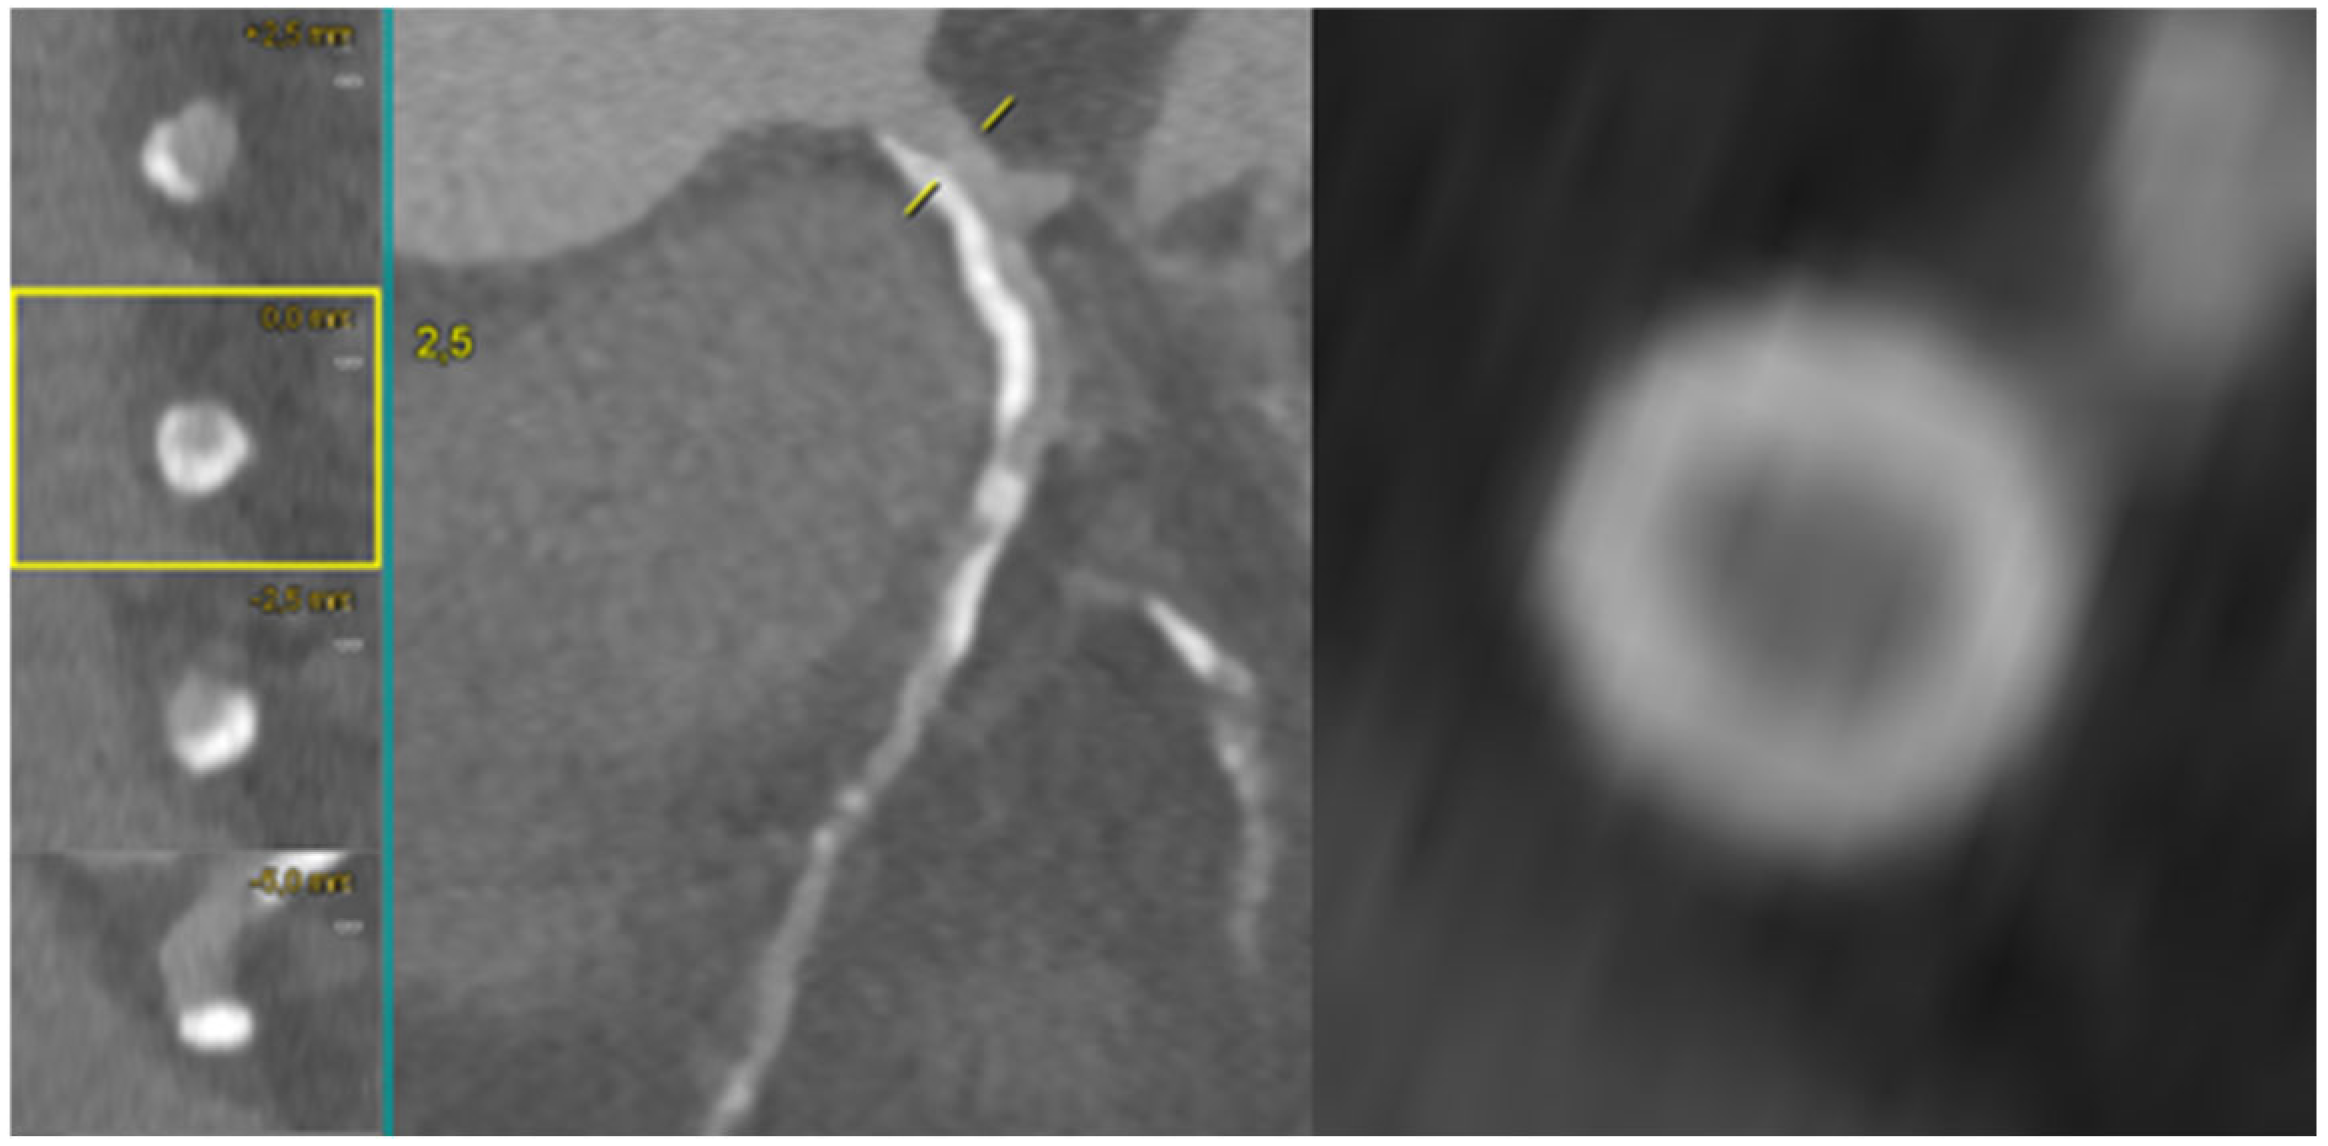

Non-invasive coronary evaluation with CCTA enables the comprehensive qualitative and quantitative analysis of atherosclerotic plaque features, lumen dimensions, and lesion length. These parameters translate directly into improved PCI planning and procedural outcomes. Plaques with a high calcium burden may lead to suboptimal stent expansion and apposition with an increased rate of target vessel failure, while incomplete plaque coverage or inaccurate lesion length estimation—often related to limited fluoroscopic projection—can result in inappropriate stent sizing and higher risk of target-vessel revascularization [2,3]. As shown in Figure 1, pre-procedural CCTA revealed a heavily calcified proximal–mid LAD lesion, with semi-circumferential to near-concentric calcium distribution on MPR cross-sections, indicative of a high calcific burden and ultimately requiring orbital atherectomy for adequate plaque debulking.

Figure 1.

Pre-procedural CCTA assessment of a heavily calcified proximal−mid LAD lesion. Multiplanar reconstruction (MPR) and cross-sectional imaging demonstrate semi-circumferential to near-concentric calcium, consistent with a high calcific burden and supporting the need for orbital atherectomy during PCI to achieve effective lesion preparation. LAD: left anterior descending.